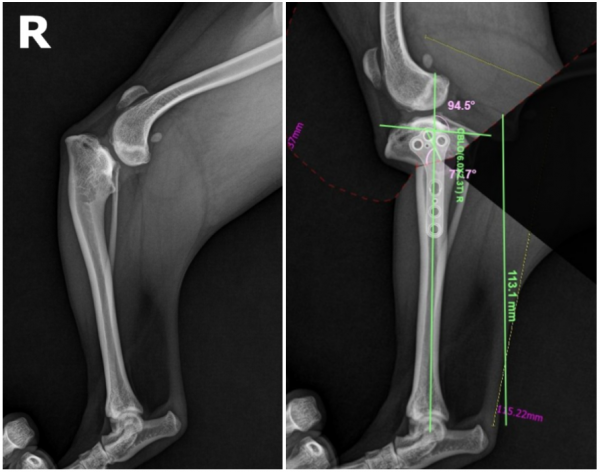

수술 전 방사선 사진

왼쪽 다리에 비해 오른쪽 다리는

강아지 경골 뒤쪽 부분이 눈에 띄게 기울어져 있는 것이 보입니다.

이렇게 뼈의 각도가 심하게 틀어져 있으면 다리가 곧게 펴지지 않을 뿐 아니라

무릎 관절과 십자인대에 가해지는 부담이 커져

통증이 지속적으로 생길 수 있습니다.

실제로 복돌이의 경우 다리가 바깥으로만

틀어진 게 아니라 함께 회전된 상태였고,

다리를 일자로 맞췄을 때 발이 안쪽으로

돌아가 있는 모습이 확인되었습니다.